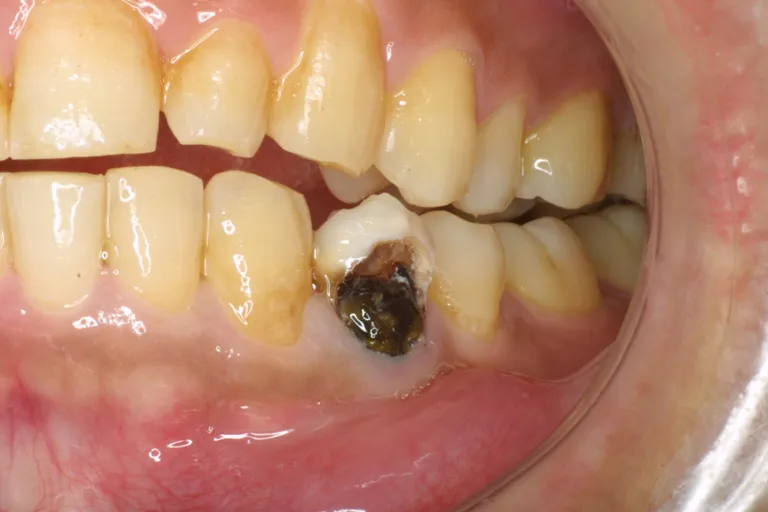

前歯のムシ歯治療前・ムシ歯のため大きな穴があいてしまっています

前歯ムシ歯治療前

保存修復治療とはその名の通り、今ある歯を「保存」しながら壊れた箇所を「修復」して「治療」する治療法です。

穴の開いた虫歯は、虫歯菌に汚染された歯質を取り除いて、詰める治療が必要です。一昔前は、アマルガムという金属を詰めました。これは、水銀を含む合金ですが、アメリカ歯科医師会(ADA)の研究でも、人体に対する副作用は、証明されていません。約100年にわたり、使用されてきた材料です。

従来型の治療では、削って型どりして作るインレーです。金属を使用したこの修復法は、詰めものを入れやすいような形に歯を削る必要があり、ムシ歯の部分以上に健康な歯を大量に削る治療でした。

現時点では、歯質に接着するレジンというプラスティックで修復することが多くなりました。特に、最近は、MI(Minimal Intervention 最小侵襲療法・治療のために削る歯をできる限り少なくします)が基本的には選択されるため、ムシ歯にかかった歯質だけを選択的に取り除き、そこにレジンを詰める治療が主流です。奥歯のかみ合わせの部分にも対応できる材料がありますので、奥歯を白く目立たないように詰めることが可能になりました。